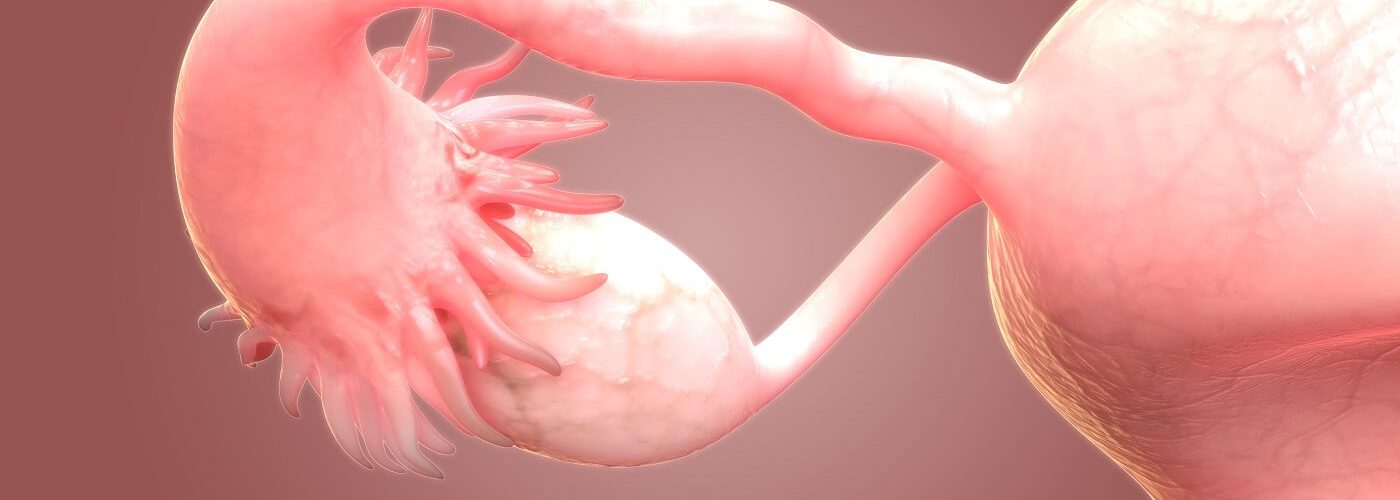

The scientists first removed the nucleus from normal skin cells and transferred them into a donor egg which had its nucleus removed. This technique, called somatic cell nuclear transfer, was used to clone Dolly the sheep in 1996.

The scientists managed to remove these extra chromosomes using a process they are calling “mitomeiosis”, which mimics how cells normally divide.

They created 82 developing eggs called oocytes, which were then fertilised by sperm via in vitro fertilisation (IVF).

After six days, less than nine percent of the embryos developed to the point that they could hypothetically be transferred to the uterus for a standard IVF process.